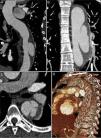

Chest computed tomography angiography (CTA) was performed to investigate the aortic disease, which revealed mild dilatation of the ascending aorta (maximum diameter 42 mm) and circumferential thickening of the aortic wall (approximately 10 mm) consistent with IMH, beginning immediately after the emergence of the left subclavian artery and involving the entire descending aorta and the proximal segment of the abdominal aorta, up to the emergence of the renal arteries (Figure 1A). It also showed a type A patent ductus arteriosus and a partially calcified atherosclerotic plaque (Figure 1B), and two ulcers in the wall of the proximal descending aorta (Figure 1C).

Initial computed tomography angiography (CTA), showing circumferential thickening of the aortic wall (arrows) consistent with intramural hematoma, beginning immediately after the emergence of the left subclavian artery and involving the entire descending aorta and the proximal segment of the abdominal aorta (A); patent ductus arteriosus (arrowhead) and a partially calcified atherosclerotic plaque (arrow) (B); two ulcers in the proximal descending aorta wall (arrows) (C).